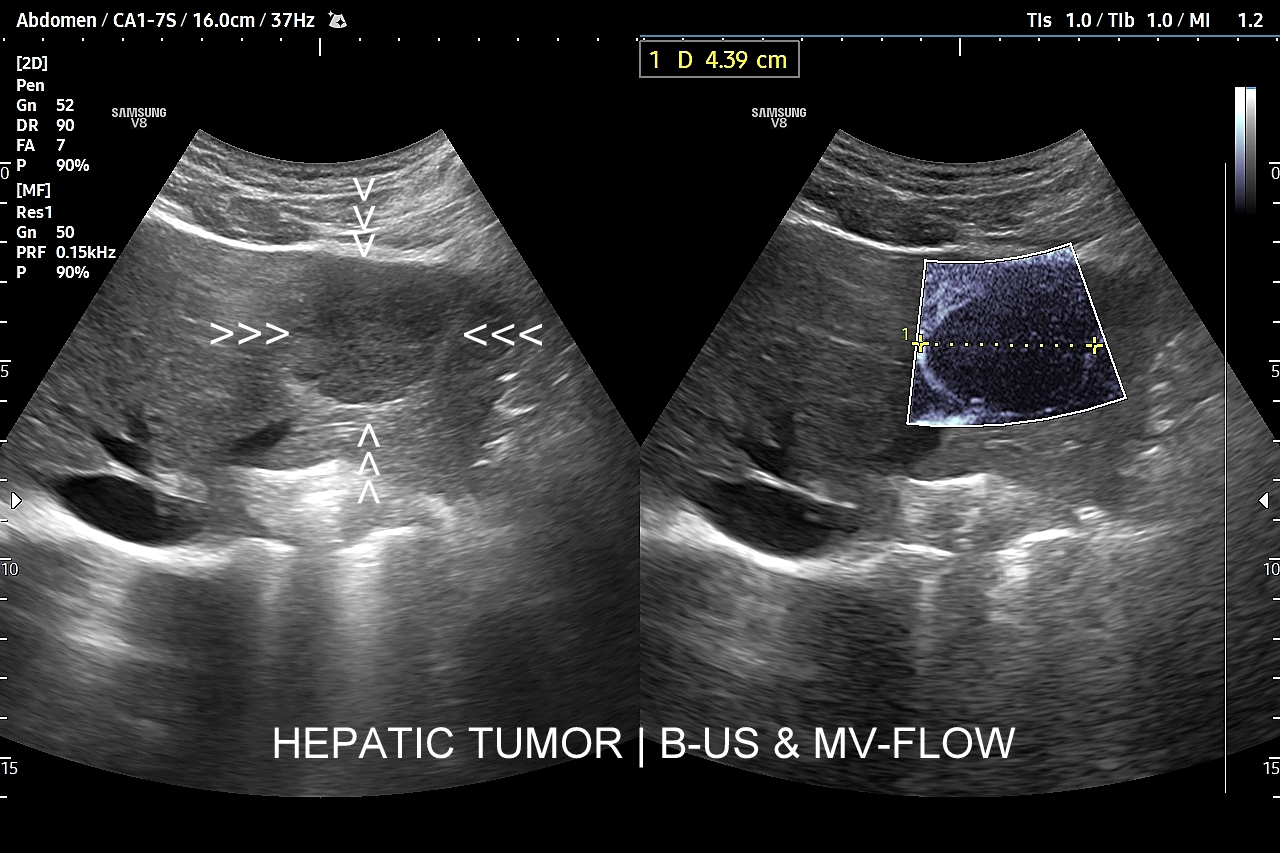

W badaniu USG w prezentacji B w niestłuszczonej wątrobie typowy naczyniak włośniczkowy lokalizuje się w pobliżu gałęzi żyły wątrobowej, a prezentuje się jako ostrookonturowana, hyperechogenna, jednorodna, krągła lub owalna zmiana ogniskowa. Ze względu na niską prędkość przepływu krwi i wynikające z tego ograniczenie detekcji w trybie color-Doppler w naczyniaku nie rejestruje się sygnału. Z kolei w trybie mikrounaczynienia (MVI / MVF) w zależności od czułości aparatury w naczyniaku można zaobserwować delikatny sygnał w postaci „poprószonego śniegu”.

W przypadku zarejestrowania w obrębie hyperechogennej zmiany ogniskowej wątroby w trybie kolorowego Dopplera lub Dopplera mocy (ang. power Doppler) drobnego naczynia lub naczyń, w szczególności krętych i o nieregularnym przebiegu, należy brać pod uwagę prawdopodobieństwo obecności złośliwej zmiany metastatycznej lub innego rodzaju zmiany ogniskowej.